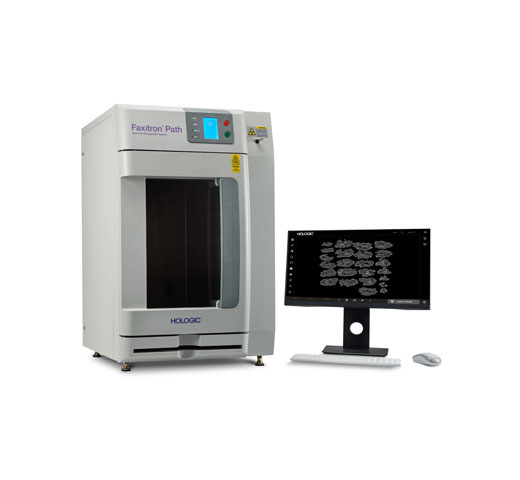

Breast Health

Hologic is transforming breast care. We apply cutting-edge science to accelerate discovery, improve efficiency and continually sharpen precision.

Time is precious when it comes to effective detection, diagnosis and treatment of breast cancer. We strive to save you time at every step along the Continuum of Care.

Browse Products